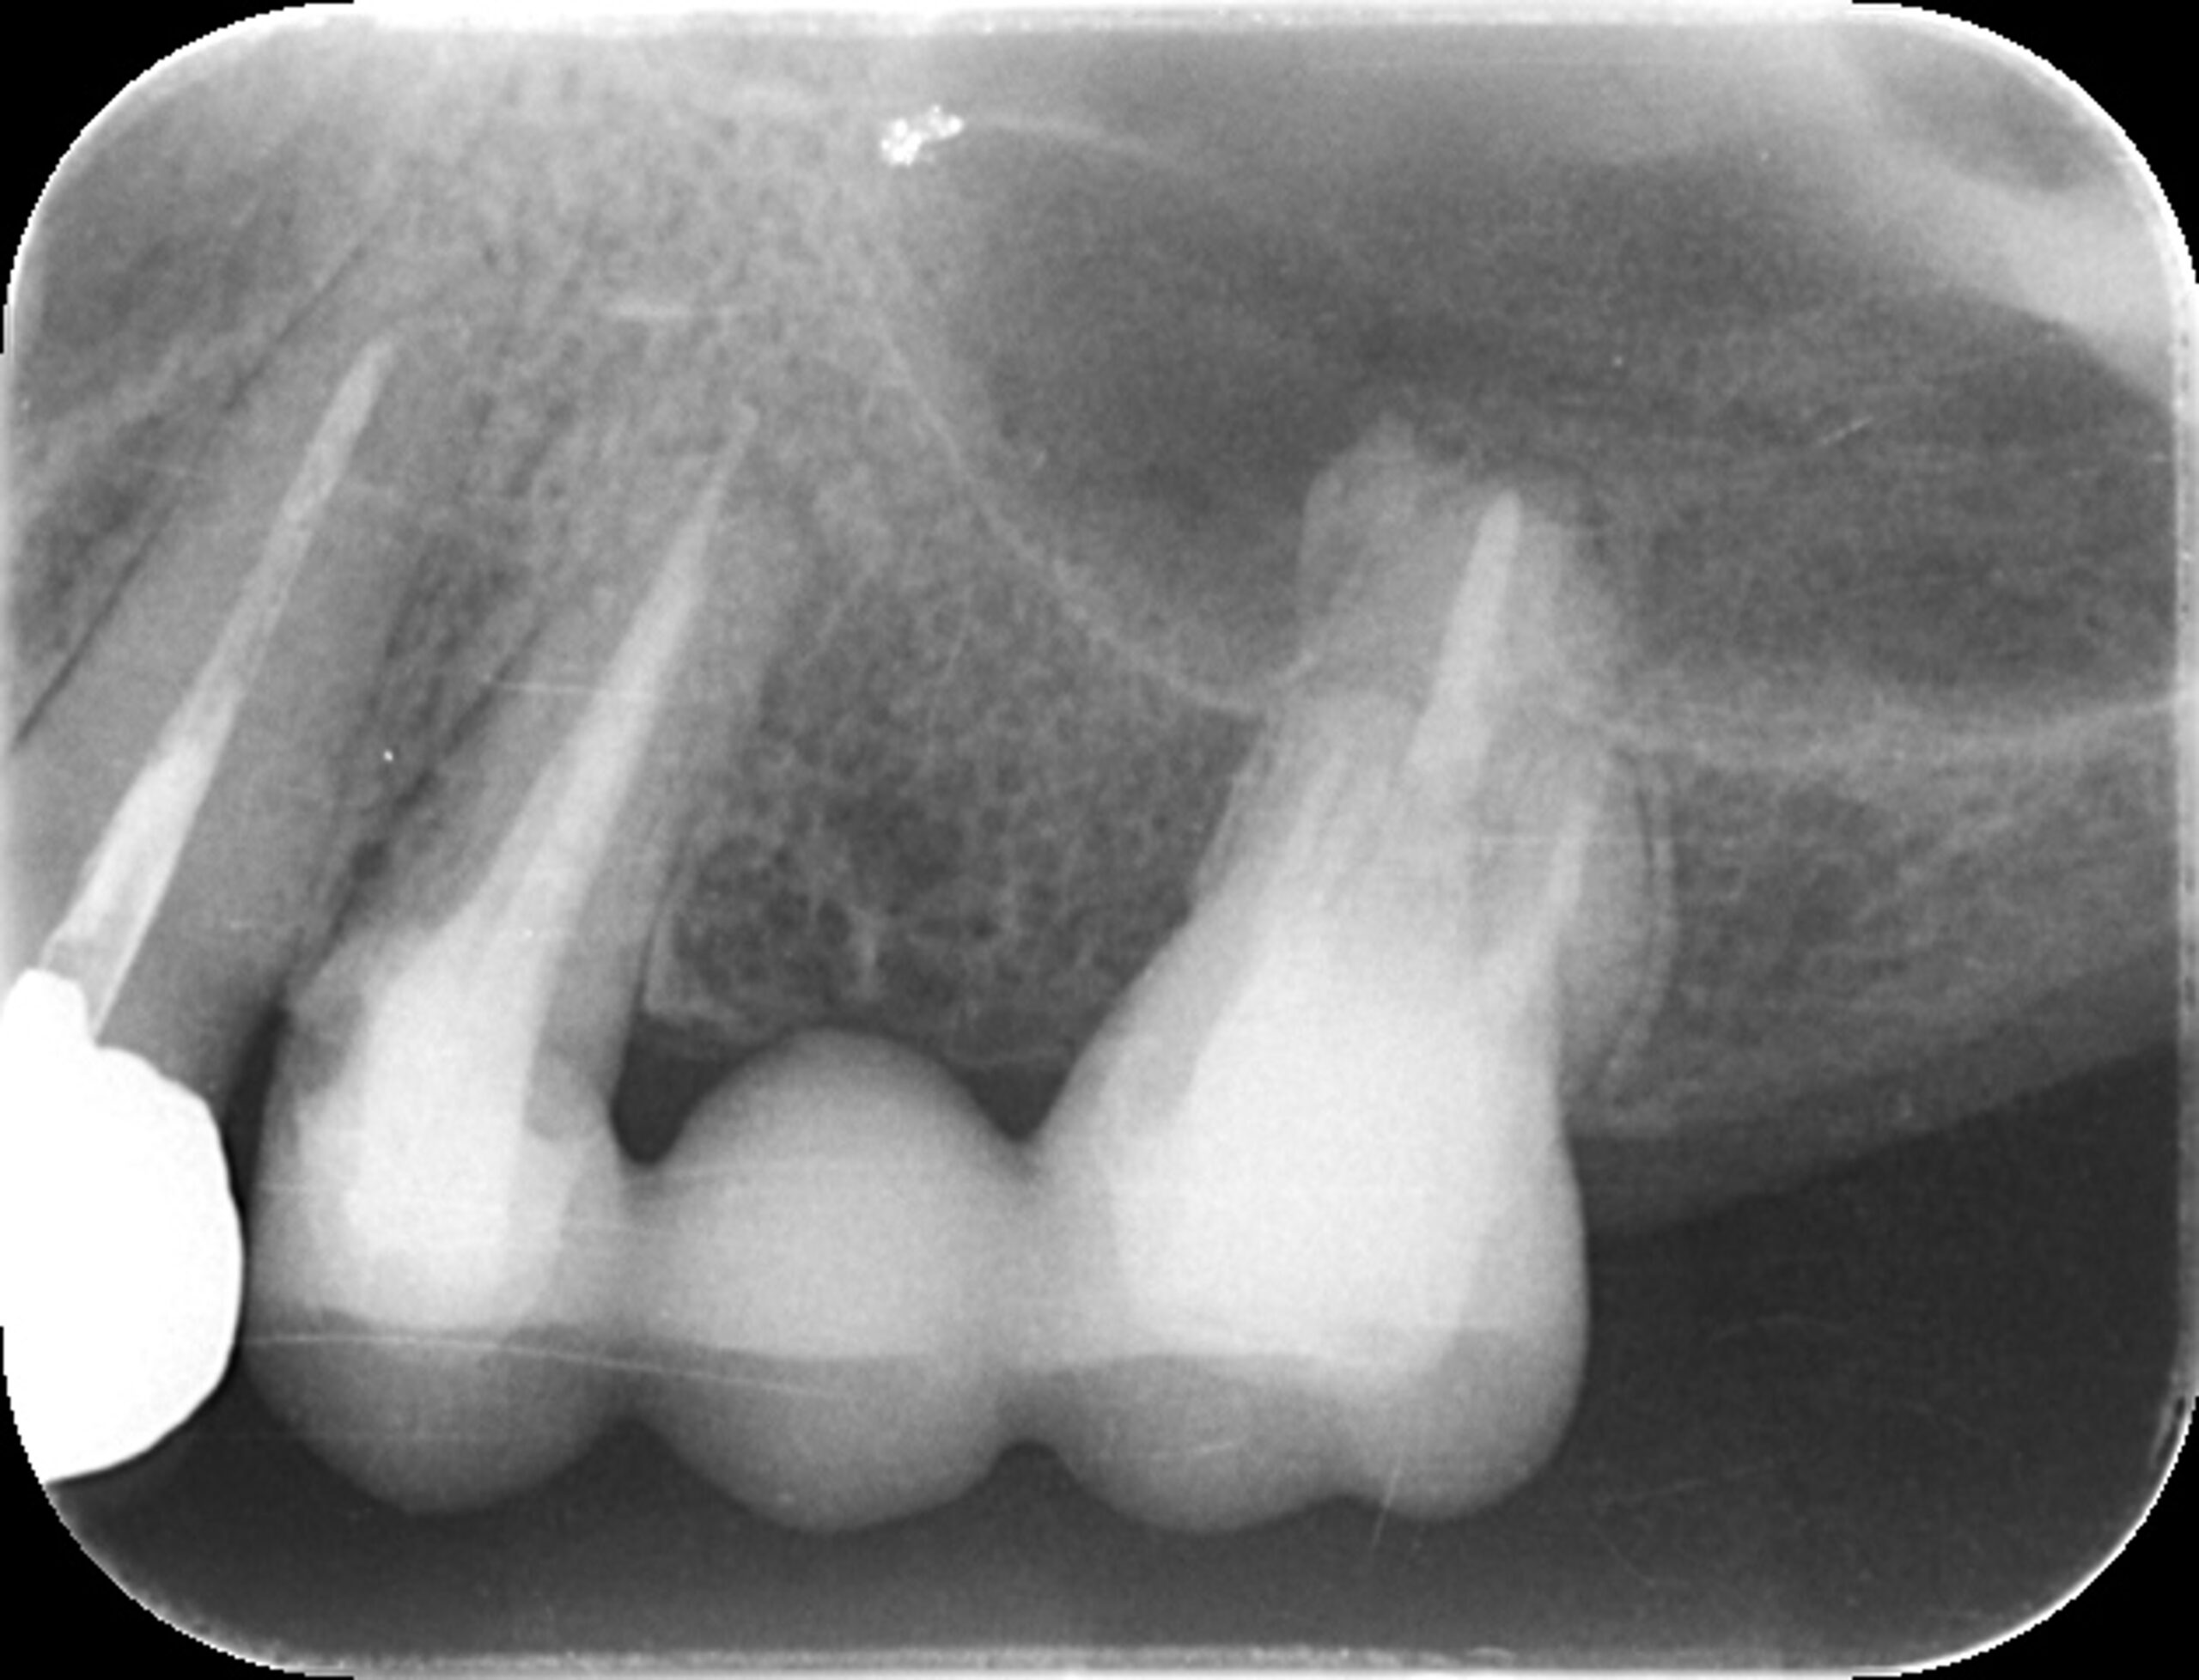

症例1

| 項目 | 詳細 |

|---|---|

| 患者様データ | 30代 女性 |

| 来院時の主訴 | 「右下の歯の治療後から違和感が続いている。」 |

| 医院の診断 | 虫歯の再発、慢性根尖性歯周炎、近心根パーフォレーション |

| 通院期間 | 6ヶ月 |

| 来院回数 | 8回(定期的なチェック含む) |

| 治療費 | 240,000円(税抜) 《内訳》 精密感染根管治療100,000円、ファイバーポストコア20,000円、セラミック治療120,000円 |

| リスクと副作用 | ①根管治療歯は長期的には破折するリスク ②メインテナンスが必要 |

| ココがこだわりのポイント☝ |

ラバーダム防湿とマイクロスコープを使用して丁寧に治療を行いました。 再根管治療のため、殺菌性があり歯を補強することのできる根管充填材料を使用しています。 |